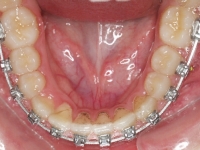

La paciente O.O. acude a nuestra consulta por:

– Canino 13 e incisivo lateral 42 en posición ectópica.

– Canino 23 incluido.

Con lo que decide realizarse un tratamiento de ortodoncia de duración de 24 meses con brackets damon Q.